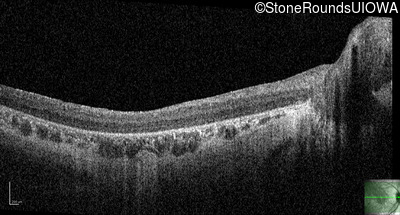

Optical Coherence Tomography - Left - 10/350 sc

Exemplar / OCT Stack